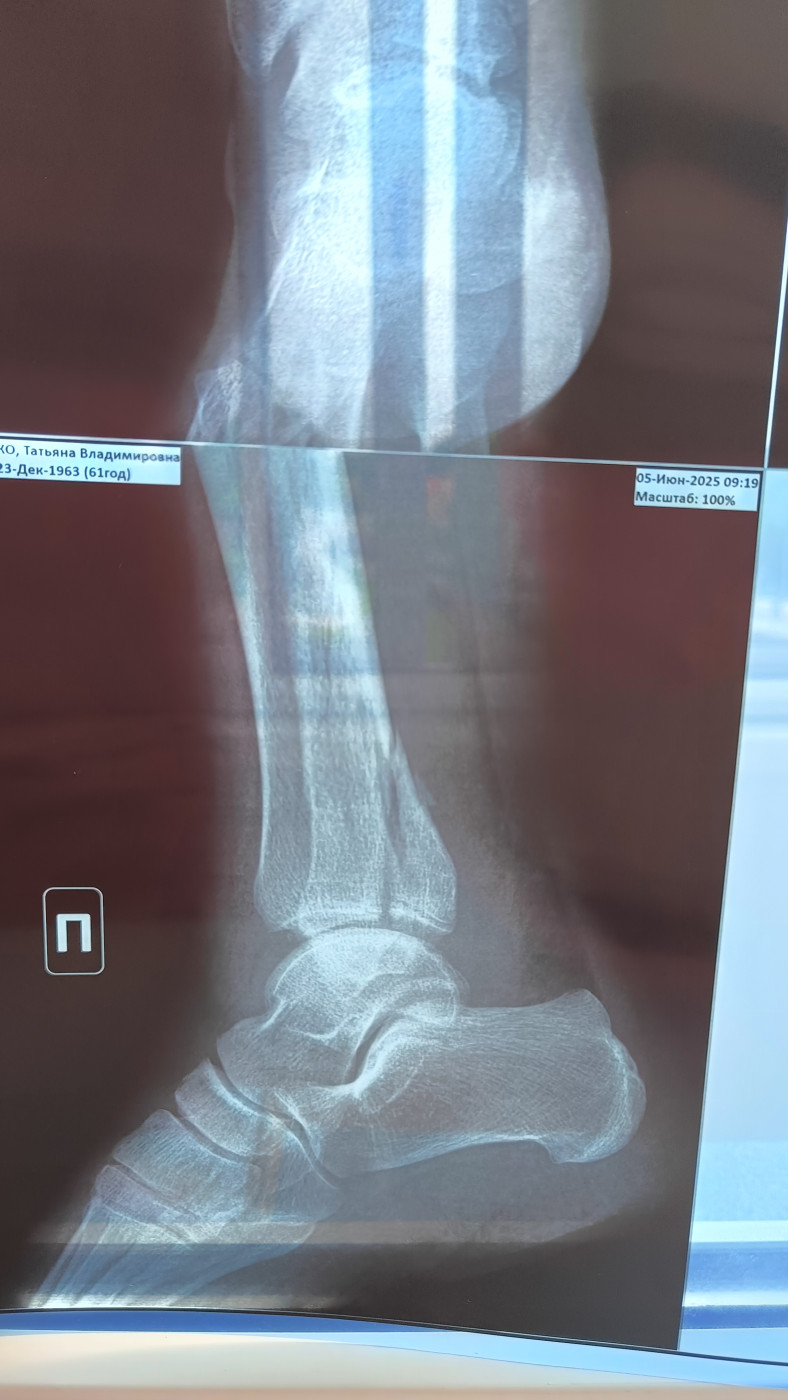

Целесообразность операции   2 ответа

Перелом правой лодыжки со смещением месяц назад, мнения врачей о необходимости операции разделились. Что посоветуете?